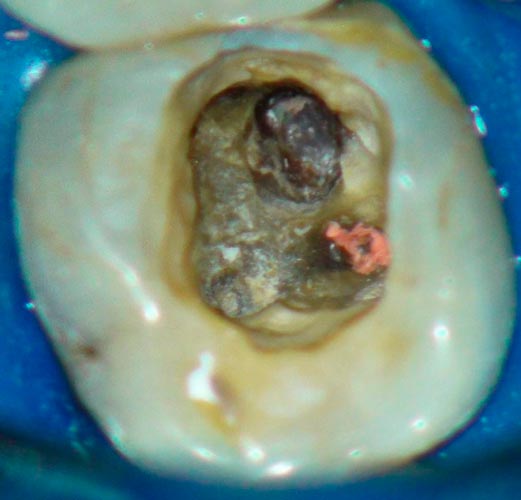

Перфорації кореневого каналу

• клініка

• діагностика

• менеджмент

Перфорації корня каналу

Класифікація перфорацій. Вплив розташування на прогноз і тактику.

Вибір матеріалу в залежності від розташування і розміру перфорації( фуркаційна, середньої третини і апікальна)

Чи є найкращий матеріал для закриття перфорації?

Правила використання композиту для закриття перфорації.

Використання біокерамічних силерів, переваги і недоліки

Сучасний «золотий стандарт» МТА? Чому МТА може не застигати? Робота з перфорацією один чи два візити? Вплив на прогноз. Відеодемонстрація роботи з різними матеріалами і різною локацією. Допоміжне обладнання при роботі з мікроскопом і без. Прогноз закриття перфорацій. Розгляд клінічних питань слухачів щодо перфорацій( підготувати клінічні ситуації). Вебінар надає 1 бал БПР,